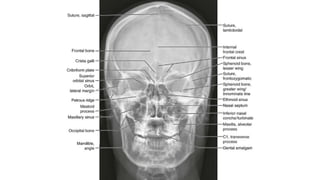

Occipitofrontal view

 This projection is used to demonstrate the frontal and

ethmoidal sinuses.

 It is also known as the Caldwell’s view.

 The patient is seated upright in front of the receptor and their

forehead and nose are placed against it.

 The beam is centred at around 15 to exit at the nasion.

⁰

• collimation

• lateral to the skin margins

• superior and inferior to the borders of the sinus cavities

Two frontal views of the skull demonstrate an incidental rounded, sclerotic lesion growing into the right frontal sinus (white arrows).